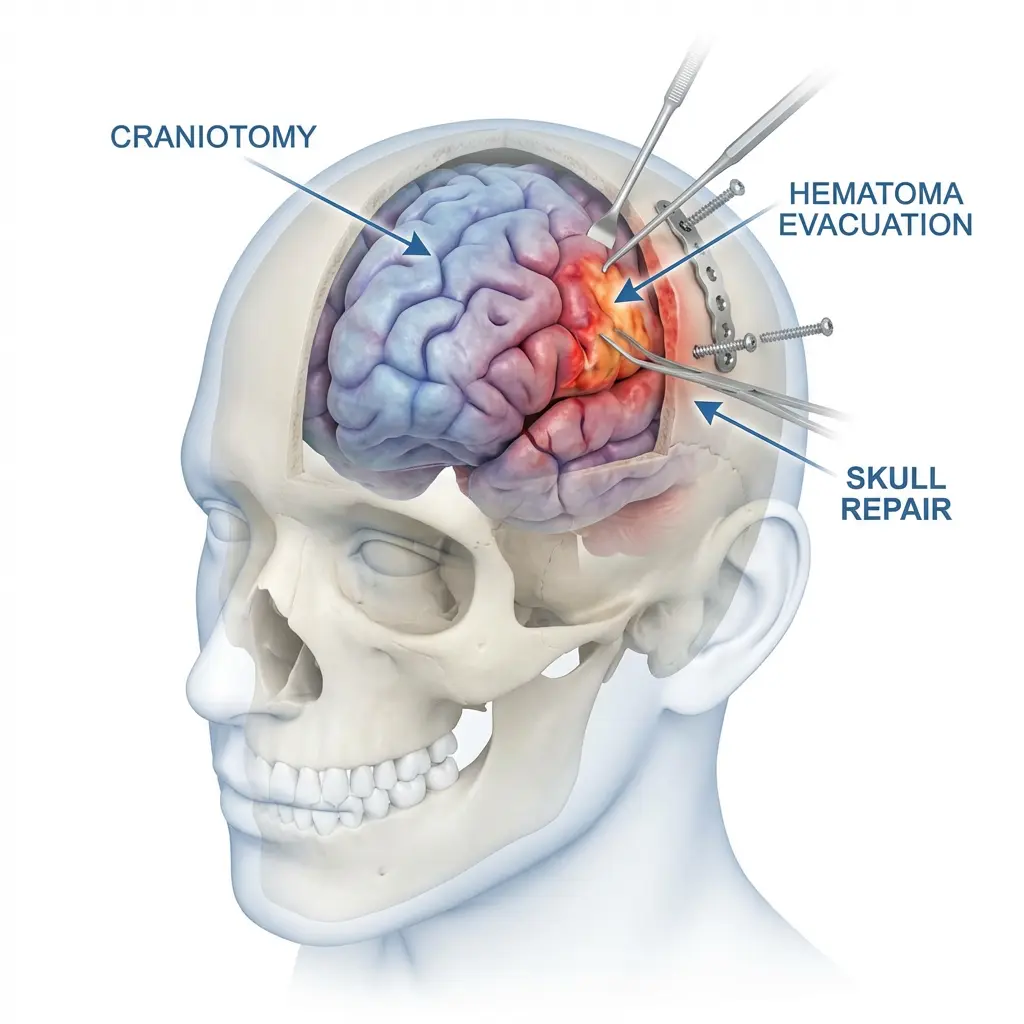

Dr Chirag Solanki, the best Neurosurgeon in Gujarat as expertise in treating a wide range of neurological conditions, including brain strokes, aneurysms, brain tumors, Parkinson’s disease, tremors, dystonia, epilepsy, pain, incontinence, psychosurgeries, spine problems and spinal tumors and traumatic brain injuries. We also offer comprehensive care options, from minimally invasive procedures to complex surgical interventions.

Actively involved in clinical and thesis-based research focusing on cerebrovascular disorders, neuro-oncology, trauma, and functional outcomes. Research work spans hospital-based studies, award-winning papers, and long-term outcome analysis aimed at improving patient care.